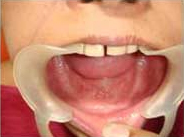

Pre Operation

Placement of Bone Grafting

After Punch Cut

Use of Bone Graft & GTR membrane for an Implant